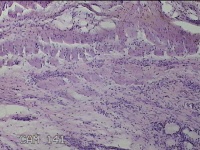

左侧外阴囊肿壁

性别

女

年龄

35岁

临床诊断

左外阴囊肿

一般病史

发现外阴囊肿2年余,加重3月。

标本名称

大体所见

灰白暗红色囊壁样组织5.5x2.8x0.7cm一堆,表面光滑,部分已切开,囊内容物已流失,囊壁厚0.1cm。

图4

具体位置,考虑巴氏腺囊肿。